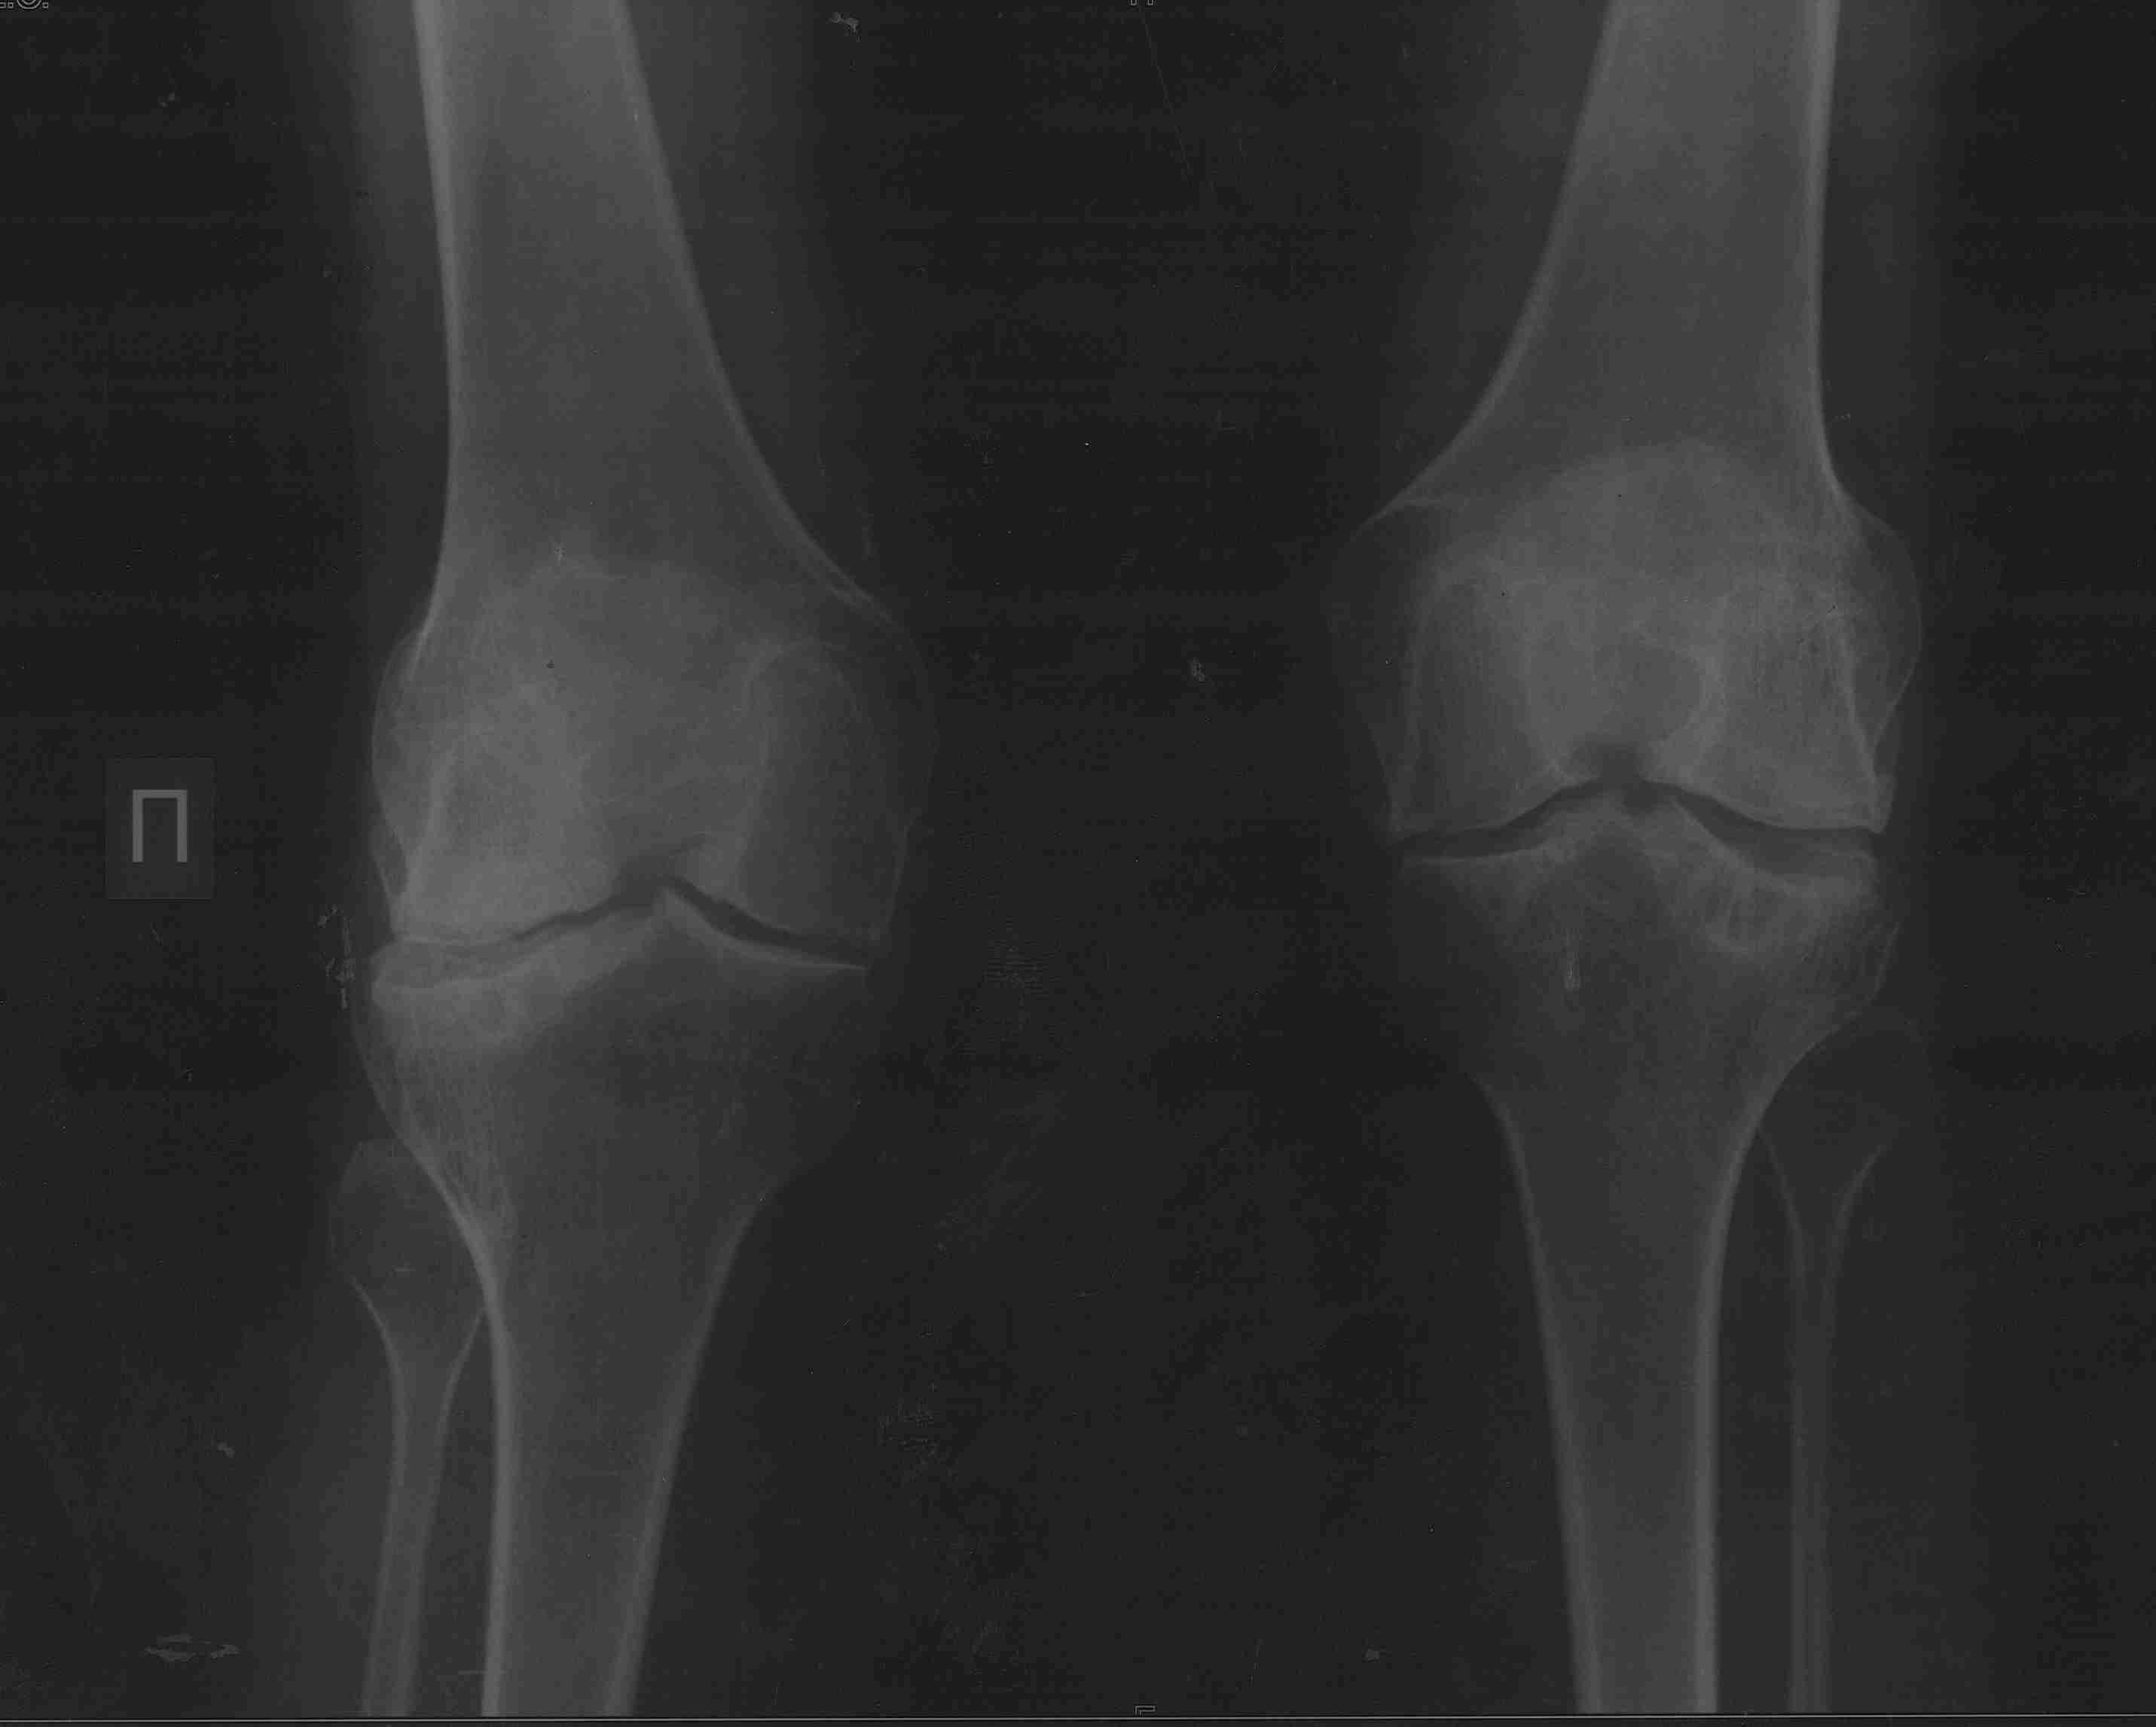

2. если да, то в каком объеме?

3. может имеет смысл сделать коррекцию ниже метафиза с одномоментной

фиксацией "приличным"гвоздем? Схема прилагается

4. насколько стоит опасаться тракционной нейропатии, стоит сделать

острое укорочение или тянуть аппаратом?